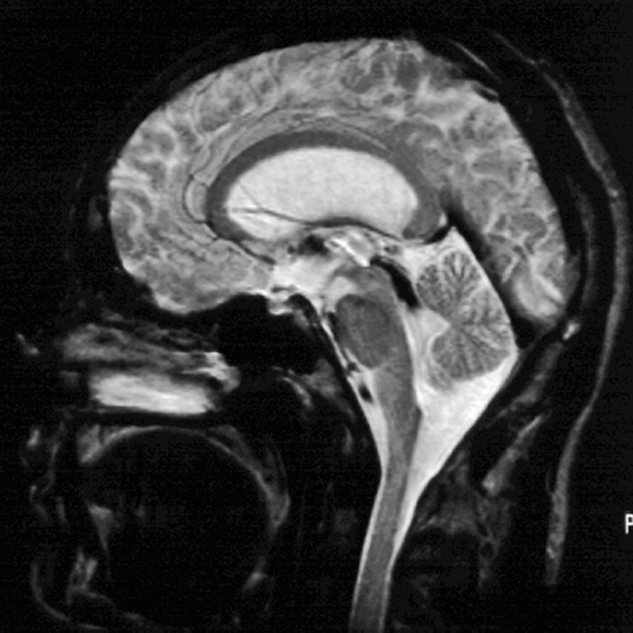

Figure 14-04:

Midsagittal slice through a normal brain. SE pulse se­quence, from (a) T1-weighted through (b) and (c) in­ter­me­di­a­te­ly weighted to (d) T2-weighted.

The fluid signal of CSF changes ac­cor­ding­ly, and the flowing blood in the straight si­nus stays black.